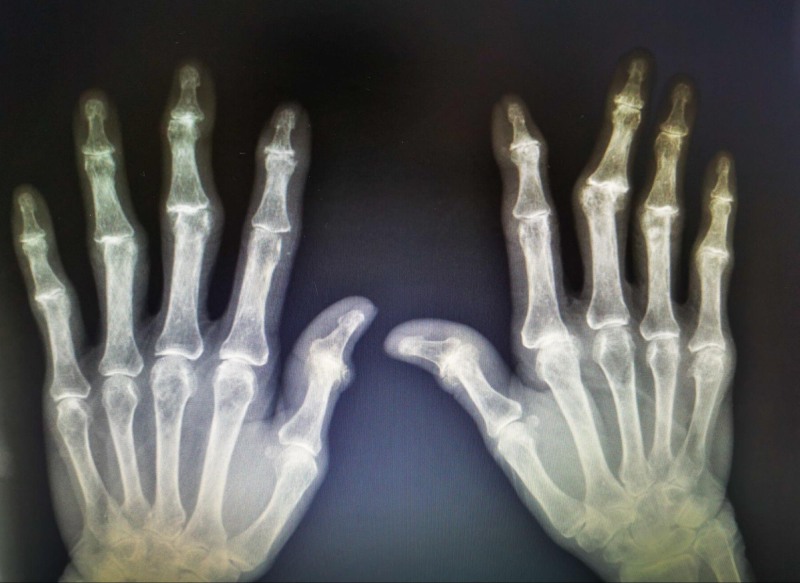

Thông thường, nồng độ RF trong cơ thể khoảng < 15 U/ml. Tuy nhiên, nếu chỉ số này tăng cao, chẳng hạn như 200 – 300 U/ml có thể là dấu hiệu cho thấy hệ miễn dịch hoạt động quá mức, thúc đẩy bệnh viêm khớp tự miễn, đặc biệt là viêm khớp dạng thấp. Tuy nhiên, nồng độ RF cao chưa đủ để chẩn đoán chính xác. Một số trường hợp viêm khớp dạng thấp nhưng vẫn có mức RF bình thường. Vì vậy, bác sĩ thường yêu cầu người bệnh thực hiện thêm các kiểm tra khác như siêu âm, chụp X-quang. (1)

RF thấp hay âm tính không loại trừ hoàn toàn bệnh viêm khớp dạng thấp. Bởi vì, khoảng 30% người mắc viêm khớp dạng thấp vẫn có kết quả âm tính khi thực hiện loại xét nghiệm này. Vì vậy, người bệnh thường được chỉ định thực hiện thêm các xét nghiệm khác như siêu âm, chụp X-quang. Để hiểu rõ hơn về RF âm tính, bạn có thể xem chi tiết tại bài viết: Viêm khớp dạng thấp huyêt thanh âm tính